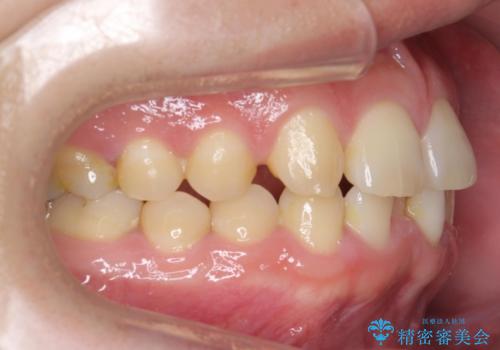

前歯のすき間 歯のがたつき

- 前歯のすき間とがたつきを主訴に来院。

右上の前歯は過去にがたつきがあったとのことで抜いてしまっていました。

歯の数を合わせるために、下の歯を1本抜いて矯正しています。

下の前歯を抜歯したことでブラックトライアングルができましたが、仕上げにIPRを加えることで目立たなくすることができました。